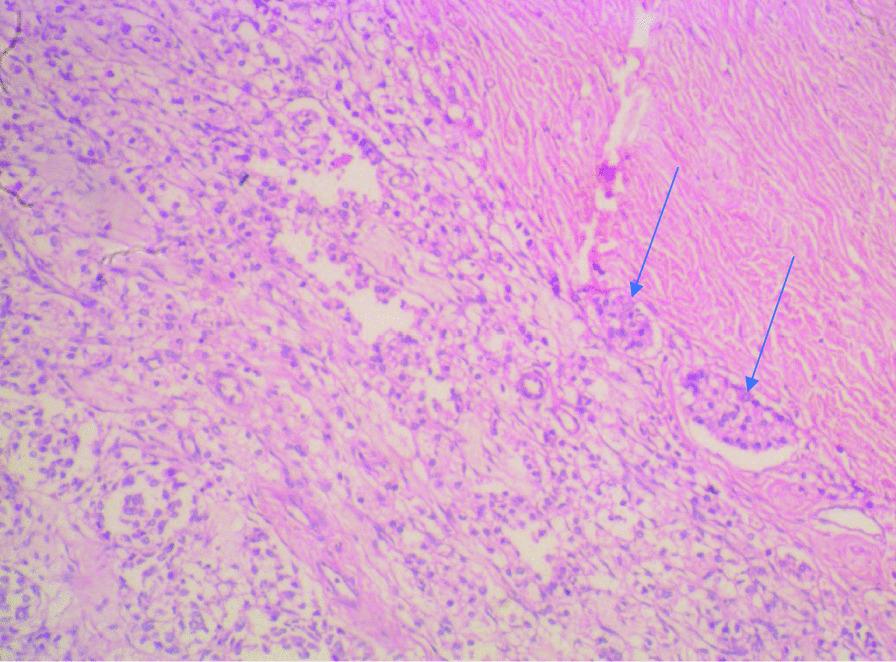

A 71-year-old Nigerian man, who presented at our hospital with 1-month-old complaints of inability to walk together with low back and bilateral thigh pains. This presentation had been preceded by a 5-month history of lower urinary tract symptoms. On examination, the prostate was hard and nodular as were the left testis and spermatic cord. On histological assessment of a needle biopsy, prostatic adenocarcinoma (Gleason score 5 + 5 = 10) was diagnosed. A subsequent therapeutic bilateral total orchidectomy specimen was found to contain metastatic prostatic carcinoma deposits, in the testes, epididymides, and spermatic cords. Although our patient is currently doing well postoperatively on zoledronic acid, ketoconazole, bicalutamide, and tamsulosin, he is being re-evaluated periodically for any feature of recurrence.

一名71岁的尼日利亚男性,因1个月来无法行走以及腰背部和双侧大腿疼痛前来我院就诊。在此之前有5个月的下尿路症状病史。检查时,前列腺坚硬且呈结节状,左侧睾丸和精索也是如此。经针吸活检的组织学评估,诊断为前列腺腺癌( Gleason评分5 + 5 = 10)。随后的双侧治疗性睾丸切除术标本发现睾丸、附睾和精索中有转移性前列腺癌沉积物。尽管我们的患者目前在接受唑来膦酸、酮康唑、比卡鲁胺和坦索罗辛治疗后术后情况良好,但仍在定期重新评估是否有复发迹象。